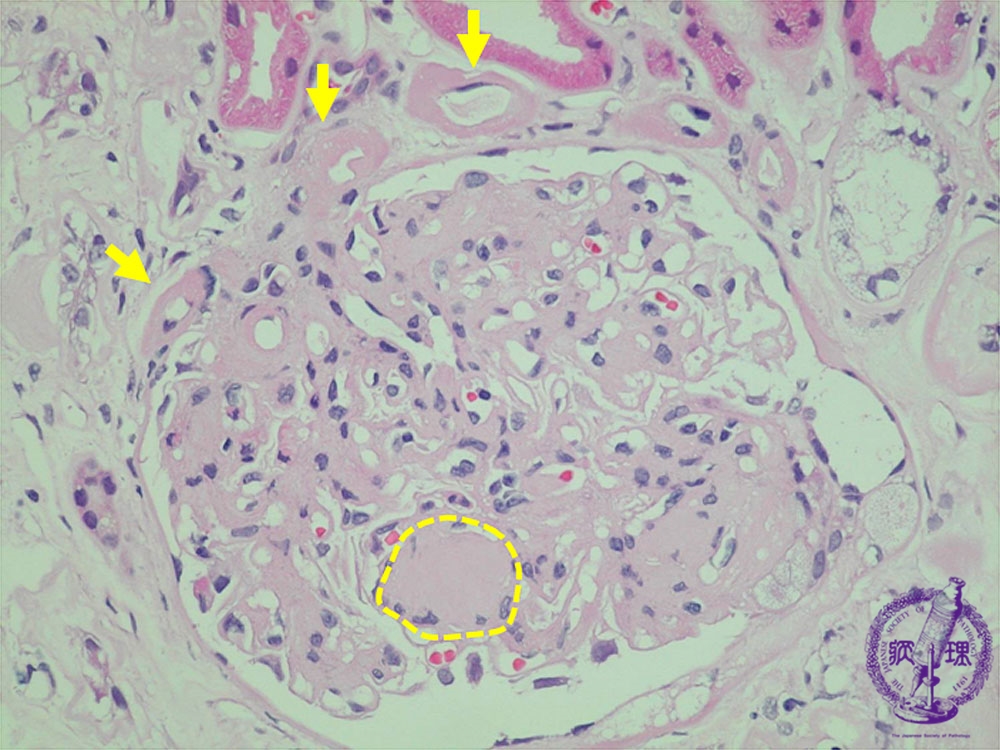

- (7)Diabetic nephropathy

Microscopic findings (HE, high power view): Nodular lesion. Eosinophilic material forms nodular deposits (yellow dotted line) within the mesangium pushing mesangial cells to the periphery, the quintesessential finding in diabetic nephropathy. There is arteriolosclerosis demonstrated by marked hyalinization in the walls of afferent and efferent arteries and arterioles. (yellow arrows).